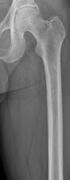

The diagnostic examination of a person with suspected multiple myeloma typically includes a skeletal survey. This is a series of X-rays of the skull, axial skeleton, and proximal long bones. Myeloma activity sometimes appears as "lytic lesions" (with local disappearance of normal bone due to resorption) or as "punched-out lesions" on the skull X-ray ("raindrop skull"). Lesions may also be sclerotic, which is seen as radiodense.[70] Overall, the radiodensity of myeloma is between −30 and 120 Hounsfield units (HU).[71] Magnetic resonance imaging is more sensitive than simple X-rays in the detection of lytic lesions, and may supersede a skeletal survey, especially when vertebral disease is suspected. Occasionally, a CT scan is performed to measure the size of soft-tissue plasmacytomas. Nuclear Medicine Bone scans are typically not of any additional value in the workup of people with myeloma (no new bone formation; lytic lesions not well visualized on nuclear bone scan).

Multiple myeloma in the upper arm

Humerus with multiple myeloma lesions

Same humerus before, with just subtle lesions